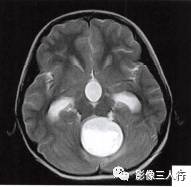

(二)影像所见

头颅MRI扫描示:小脑上蚓部见团块状异常信号影,边缘清楚,大小约4.5cm×3.5cm×3.7cm,T1WI(图B)等信号,中心可见更低信号,T2WI(图A)呈髙信号,水抑制(图C) 等信号,中心呈更低信号,周边可见轻度高信号水肿区。增强后(图D〜F)病灶可见明显环形强化,壁较厚,内壁欠光滑,邻近小脑及第四脑室受压,第三脑室、双侧脑室扩张积水。

诊断:小脑上蚓部占位,考虑肿瘤性病变,以毛细胞型星形细胞瘤可能性大。